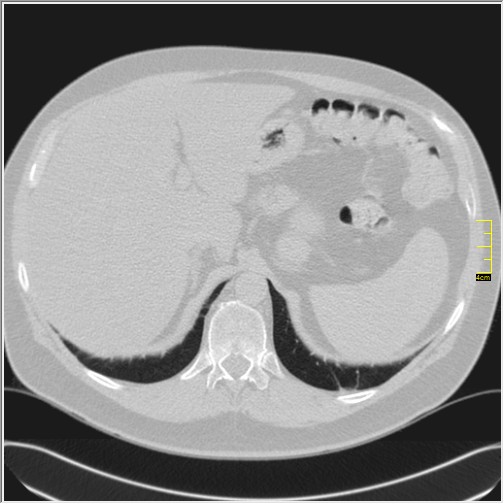

Četiri dana kasnije. Isti pacijent dolazi sa istim pulmologom. Situacija je sada sasvim drugačija. Temperatura 39.5 C. Saturacija 92. Laboratorija daleko gora. Uradim CT pluća. Ovo je izašlo.

Severity score 15/25. Pacijent je upućen na bolničko lečenje.

Ono što zbunjuje, a to se ponavlja zadnjih 10 dana, je da fibroza nastupa u progresivnoj fazi, znači na početku bolesti. Toga nije bilo do sada. Sledećih dana ću o tome.

Ovo je samo 4 dana. Od zdravlja do teške bolesti. Pacijent je 45 godina starosti, očigledno nije povećane težine, kaže za sebe da je bio sportista. U anamnezi nije naveo nikakve bitne bolesti.